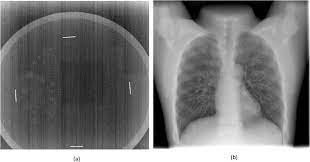

Pdf Digital Chest Radiography With A Large Area Flat Panel Silicon X Ray Detector Clinical Comparison With Conventional Radiography

Pdf Digital Chest Radiography With A Large Area Flat Panel Silicon X Ray Detector Clinical Comparison With Conventional Radiography from www.researchgate.net